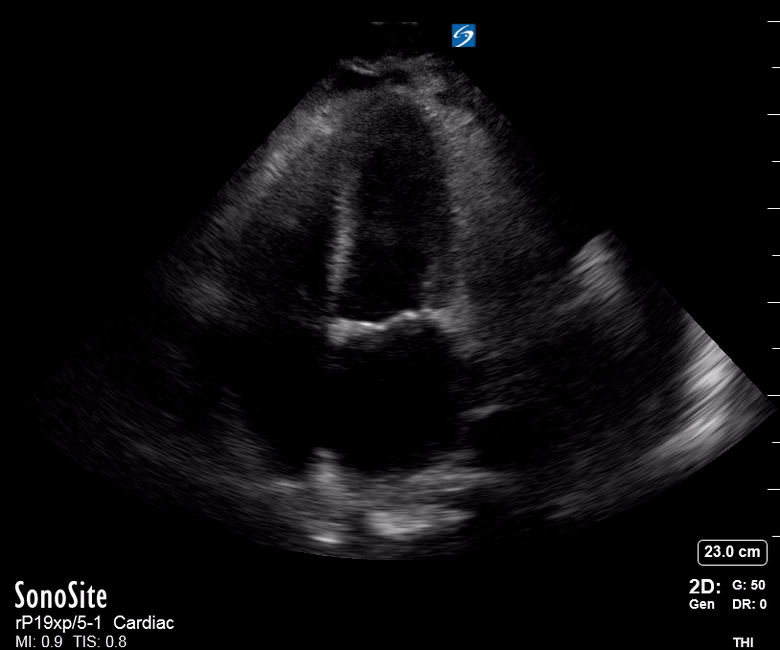

Equality: is the RV dilated or significantly impaired?

Normally, the RV is a low-pressure, thin-walled, high-compliance chamber that wraps anteriorly around the muscular, cone-shaped LV. The normal RV : LV diameter ratio is 0.6 : 1.

When the pulmonary artery pressure rises, the RV will dilate, altering the normal RV:LV ratio. Although sacrificing sensitivity, the use of equality (1:1 ratio) as a cutoff can achieve a specific estimation of RV strain. If imaged correctly by a trained operator, the presence of an RV:LV ratio > 1 is highly specific for RV strain.

RV dilation can be acute, chronic, or acute-on-chronic. However, in patients presenting with undifferentiated chest pain, shortness of breath, hypotension or syncope, the presence of any RV dilation should raise suspicion for acute pulmonary embolism (PE). Furthermore, in a patient in shock, the presence of RV strain may signal the need for aggressive therapy – emergency thrombolysis.

THE VIEWS

The A4C view provides an accurate chamber size comparison. However, achieving a proper A4C view (avoiding foreshortening or ballooning, and visualising the four chambers with a vertically oriented interventricular septum) can be a challenging exercise of image acquisition. Additionally, the PSAX view at the level of the papillary muscles shows both LV and RV side by side and is useful to assess function and size. When RV pressure is high, the septum will be pushed and flattened towards the LV, resulting in the characteristic “D-shaped” LV or “D sign”.